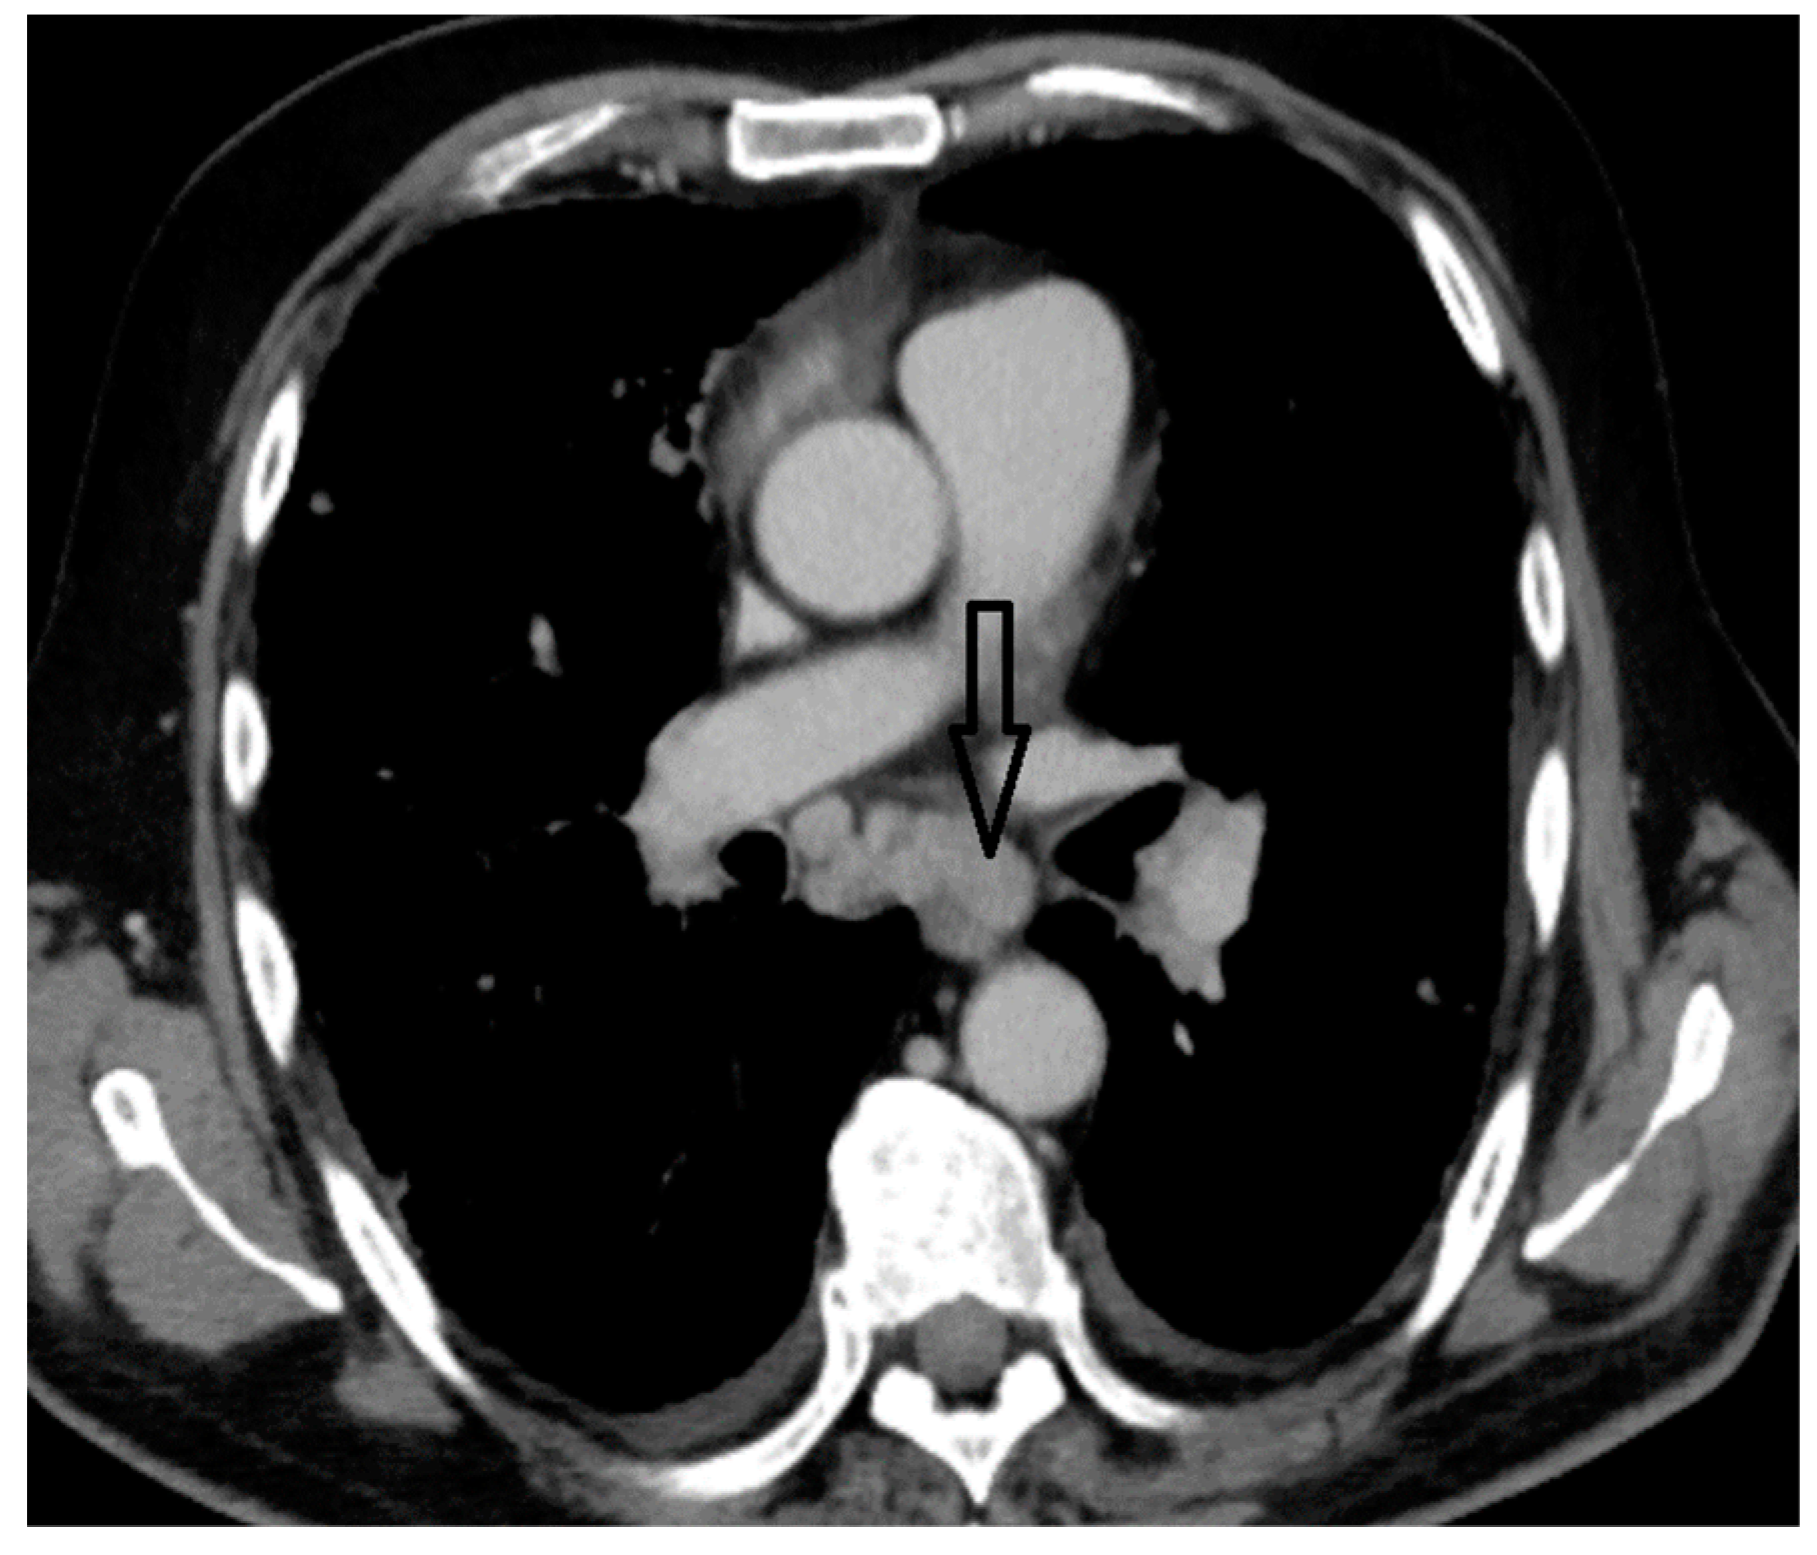

A whole-body contrast enhanced CT scan was subsequently performed, which demonstrated a 6/2.8 cm heterogeneous cervical mass that enclosed the left thyroid lobe and isthmus, as well as the posterior side of the sternocleidomastoid muscle (with no clear demarcation line), and superior extension to the larynx and to the thyroid cartilage. Inferiorly, invasion to the superior mediastinum structures was noted. Chest CT revealed multiple bilateral pulmonary nodules, suggestive of metastasis, and lymphangitic carcinomatosis. Several cervical and mediastinal lymph nodes with a tendency to confluate were also involved (Figure 1, Figure 2, Figure 3 and Figure 4).

Figure 4.

Mediastinal adenopathies.